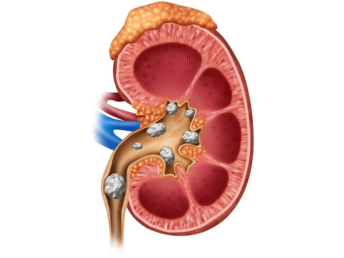

Kidney Stones

02. Stone removal and urinary tract management.

Effective treatment for kidney and urinary stones along with complete care for infections, obstructions, and bladder disorders.